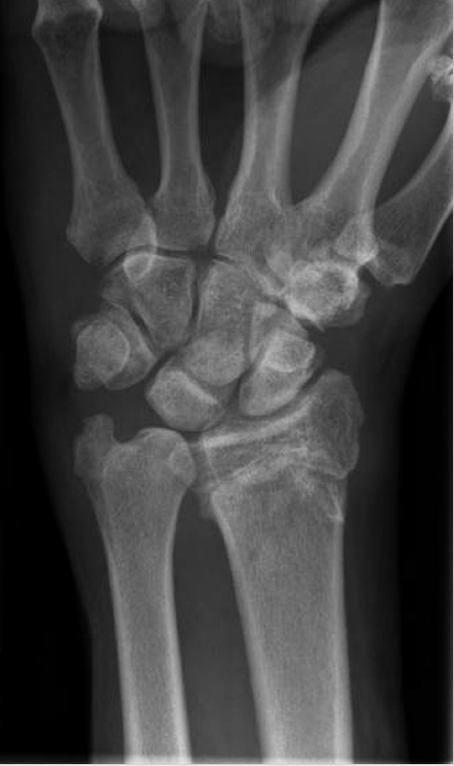

The wafer procedure is considered for patients who present with ulnar-sided wrist pain from ulnar impaction syndrome. Their pain is typically aggravated by forceful grip, forearm pronation, and ulnar deviation. Clinical examination may reveal swelling over the dorsal wrist with tenderness to palpation over the ulnocarpal joint and triquetrum and decreased range of motion. Other causes of ulnar-sided wrist pain must be ruled out, including lunotriquetral (LT) pathology, DRUJ arthritis, DRUJ instability, hook of the hamate injury, extensor carpi ulnaris(ECU)subluxation, andpisotriquetraljointinjuryorarthritis. Imaging studies begin with three view X-ray of the wrist which can reveal ulnar positive variance (► Fig. 60.1) and possible cystic changes of the lunate and/or triquetrum. Ulnar impaction is frequently associated with tears of the TFCC, 6 which can be evaluated by magnetic resonance imaging (MRI), magnetic resonance arthrogram, and/or arthroscopy. For a successful wafer procedure, no more than 4 mm of the distal ulna is resected, or the procedure will result in removal of the majority of the ulnar head articular surface in contact with the sigmoid notch, potentially compromising the DRUJ articular surface.

With a three view X-ray of the wrist, ulnar variance is measured on the A/P X-ray with the wrist in neutral rotation. This is achieved with the shoulder abducted at 90 degrees, elbow flexed at 90 degrees, and the forearm and palm flat on the X-ray cassette. A true A/P X-ray can be confirmed by identifying the location of the ECU groove radial to the long axis of the ulnar styloid. The measurement is performed by drawing a line through the volar sclerotic line of the distal radius and perpendicular to its long axis. The distance between this line and the cortical margin of the ulnar dome is then measured as ulnar variance. Ulnar positive variance can be further exacerbated by X-ray performed with the patient in power grip or with the forearm pronated. Ulnar height increases on average 0.4 mm with forearm pronation versus neutral, and this difference may not be clinically significant, 7 but ulnar height can increase an average of 2 mm with a power grip in pronated position. 8 An X-ray of the contralateral wrist is performed for anatomic comparison. Cystic changes and osteophytes of the lunate, triquetrum, and distal ulna usually best seen on PA view are sequelae of long-term ulnar impaction. The DRUJ and LT intervals must also be visualized. Widening or incongruity of either joint or volar intercalated segmental instability (VISI) deformity is consistent with instability and would raise other causes of wrist pain and concern that ulnar wafer resection would be inadequate treatment for the patient.